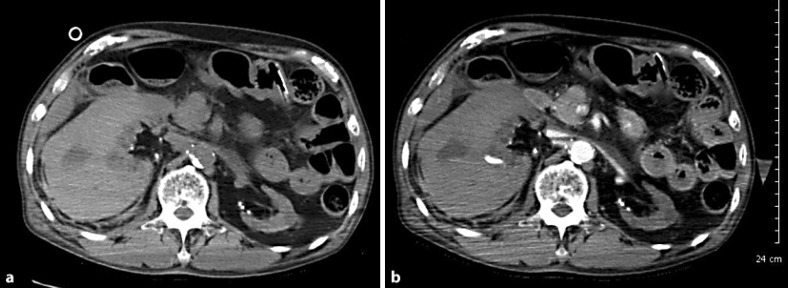

Dialysis patients have a tendency to bleed, and clinicians sometimes encounter cases with a significant amount of spontaneous hemorrhage. We herein report two cases of spontaneous renal hemorrhage in hemodialysis patients. CASE 1: A 70-year-old male who had received hemodialysis for 8 years presented with right abdominal pain. He had a history of renal failure due to diabetes mellitus. CT showed a right perirenal hemorrhage. Angiography revealed a right renal artery hemorrhage, and catheter embolization was performed. CASE 2: A 76-year-old male who had undergone 7 years of continuous ambulatory peritoneal dialysis and 1 year of hemodialysis presented with right abdominal pain. He had a history of renal failure due to IgA nephropathy. CT showed a right perirenal hemorrhage. He received a blood transfusion and was put on absolute bed rest. At 2 days after admission, his anemia was found to have improved.